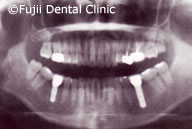

| 術後パノラマ写真および口腔内写真 |

ヘビースモーカーであったために、禁煙してもらい、歯のクリーニングやブラッシング指導後、およそ2年間かけて左上犬歯と左下第一小臼歯以外すべての歯を抜歯し、インプラントの埋入手術を行いました。左右上顎臼歯部はサイナスリフトなどを併用し、インプラントによる咬合の再構築を試みました。